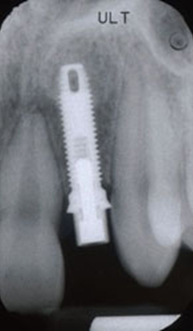

Зъбните импланти са изкуствени зъби от титан, които се присаждат в челюстта.

Поставянето на зъбни импланти е рутинна дейност в нашата практика. То се извършва след предварително рентгенологично изследване и внимателно планиране. Имплантирането се извършва гарантирано безболезнено под местна упойка, но при страхливи пациенти по тяхно желание може да бъде и под обща упойка. Поставянето на зъбен имплант (присаждане на зъб) е по-малко травматично за пациента от изваждане на зъб.

За период от 2 до 6 месеца зъбният имплант се интегрира в костта, след което се пристъпва към поставяне на необходимата конструкция - коронка, мост или протеза. Днес има и импланти, които по преценка на лекуващия лекар се натоварват веднага – т.е. не се изчаква имплантатът да се интегрира, а веднага след поставянето му се слага коронката.